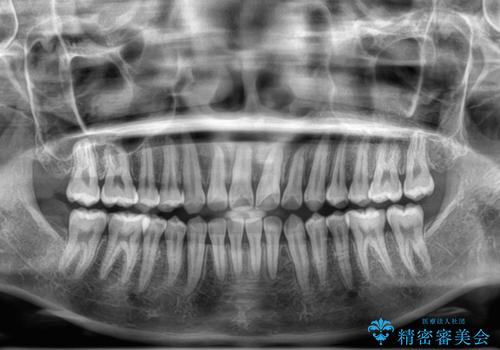

- 上下前歯のデコボコを気にして来院された患者様です。

ワイヤー矯正でもマウスピース矯正でも可能でしたが、短期間で、自身の手を煩わせることなく治療を行いたいとのことで、ワイヤー装置にて矯正治療を行うこととしました。

僅か半年強、あっという間に治療を終えることができました。